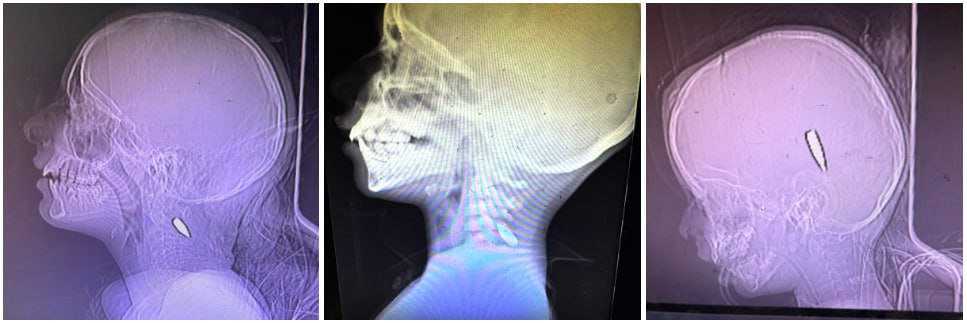

#어쩌다 <뉴욕타임즈>에서까지 보도됐듯, 학살된 🇵🇸 유아들의 많은 X레이 사진들도 정확하게 머리와 목에 총알을 명중시킨 저격수들의 작업을 꾸준히 증거해왔고.

RT) 수업에서 란츠만의 <쇼아>를 경유해 유대인 절멸과 🇵🇸 문제를 다룰 때 종종 강조하지만, '가자' 문제는 '누가 먼저냐' 논쟁을 사실 지났고, 유아를 포함한 🇵🇸 아이들과 이들을 '생산'하는 '종적 거푸집 ethnic matrix'인 가임 여성들의 '체계적 절멸'에 맞춰져 있다는 걸 놓쳐선 안된다.